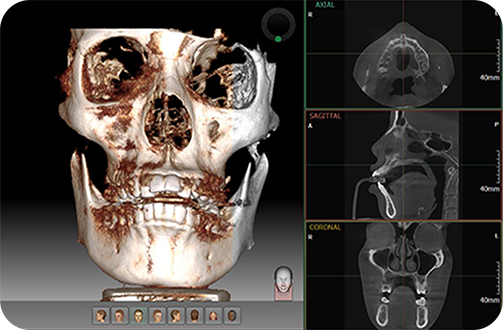

제이준 사각턱축소술

3D CT장비를 이용한 수술전 과학적 검사

3D정밀진단시스템

3차원 3DCT(X-RAY)영상촬영을 통해

뼈의 두께, 넓이, 신경과 혈관의 위치 측정 등

정확한 계측을 통해 오차 범위 최소화하여

안전하고 만족스러운 수술결과